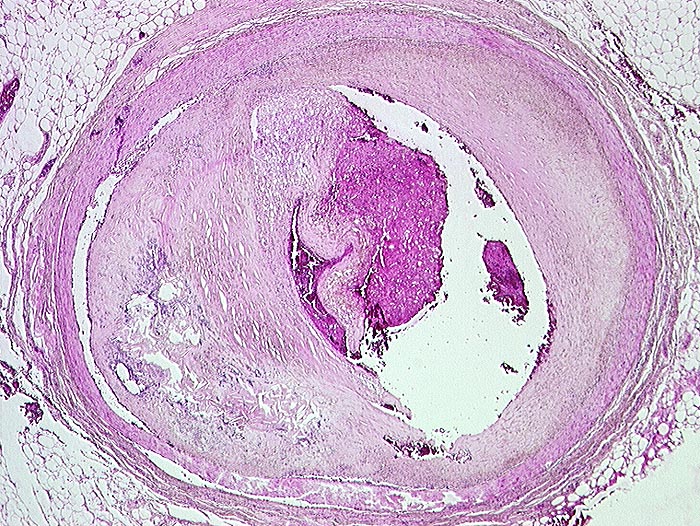

PathoPic ID 99 - frischer Deckplattenaufbruch

frischer Deckplattenaufbruch

vaskulär / Durchblutungsstörung

Arteria coronaris

Kardiovaskuläres System

Auf der abgerissenen Deckplatte hat sich eine kleine Thrombose gebildet

Transmuraler akuter Myokardinfarkt bei Deckplattenaufbruch des RIVA mit Thrombose.

Diabetes mellitus Typ II.

Adipositas.